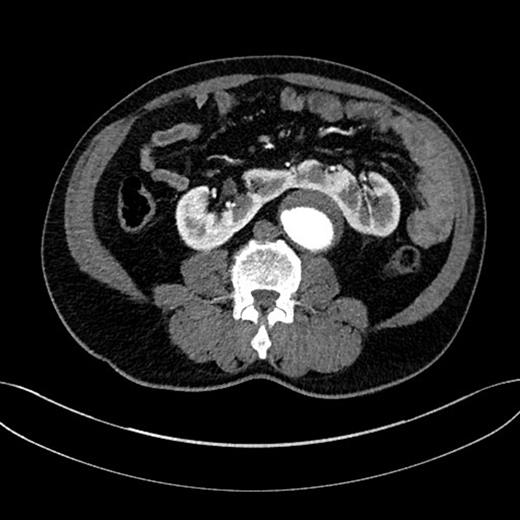

A 67-year-old man, with a known AAA of 4.42 cm, was found to have expansion of the aneurysm diameter to 5.40 cm after undergoing a 3-month surveillance ultrasound scan. The patient's aneurysm was further investigated by a computed tomography angiography (CTA), which demonstrated a 5.50 cm juxtarenal AAA that was not suitable for endovascular AAA repair (EVAR) because of a severely angulated proximal neck. The aneurysm contained a significant amount of mural thrombus. Moreover, the CTA demonstrated a HSK anterior to the abdominal aorta (Fig. 1). Following a multidisciplinary team discussion, an open repair with involvement of both vascular and urology surgeons was decided.

(a) HSK (the isthmus), (b) the distal segment of aneurysm close to the iliac bifurcation, (c) the aneurysm neck, (d) the left renal vein and (e) the left ureter.